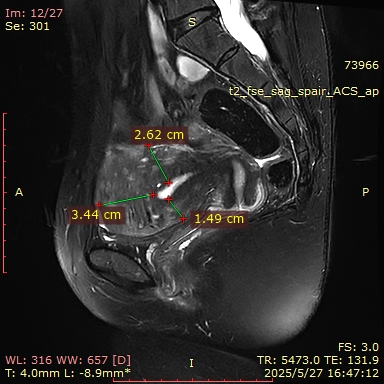

MRI(2025-05-27):子宫肌层增厚,其内信号欠均匀,肌层内见一等类圆形T2WI低信号,其内可见T1WI高信号,大小约为40mm*39mm。左侧附件区可见类圆形短T2异常信号影,大小约为8mm*5mm;右侧附件形态、大小、信号未见明显异常。盆腔少量积液。